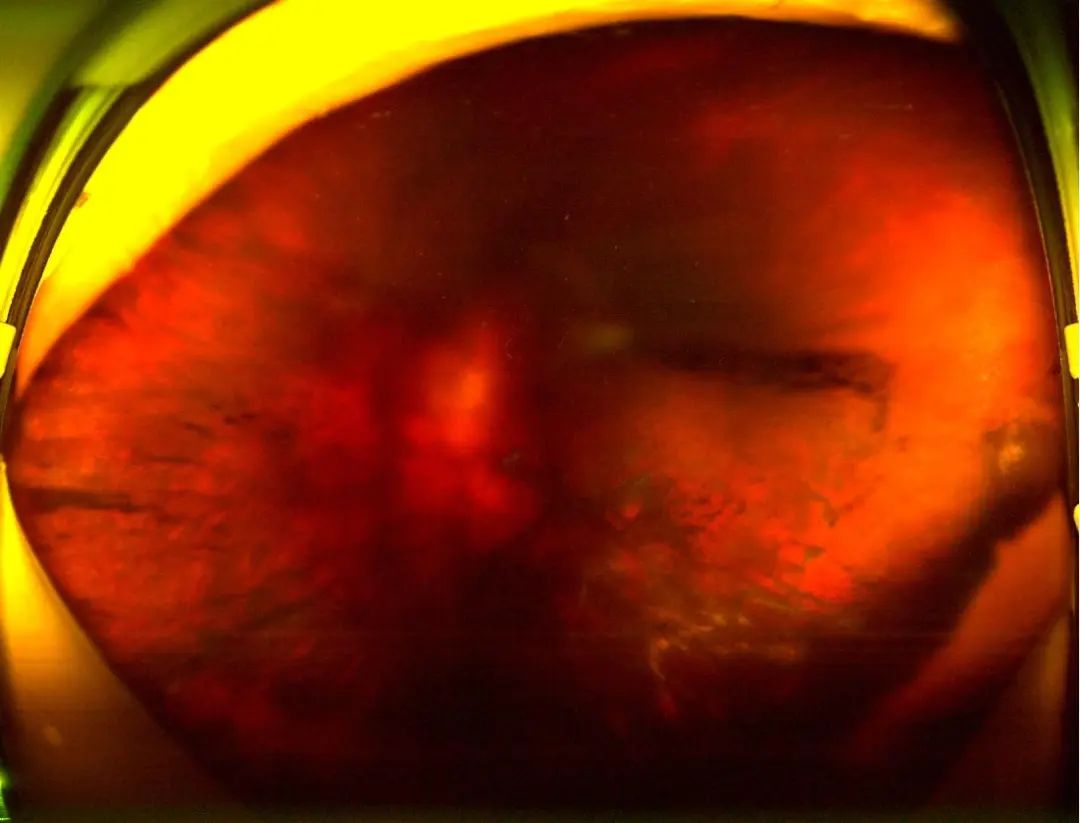

▲图三:左眼玻璃体积血眼底照相图

这一系列复杂的眼疾,如同沉重的枷锁,紧紧束缚着她对光明的向往。尤其是左眼,因玻璃体积血已超一月,视力几乎降至手动,逼近失明的边缘。

面对如此棘手的病情,岳阳爱尔眼科医院的专家团队迅速行动起来。他们检查发现,周阿姨的双眼眼轴长度异常,达到了29mm,远超正常人的24mm,近视度数更是惊人地达到了1600多度,属典型的“病理性近视”。这种近视不仅影响视力,更可能引发多种眼底病变,手术难度极大。